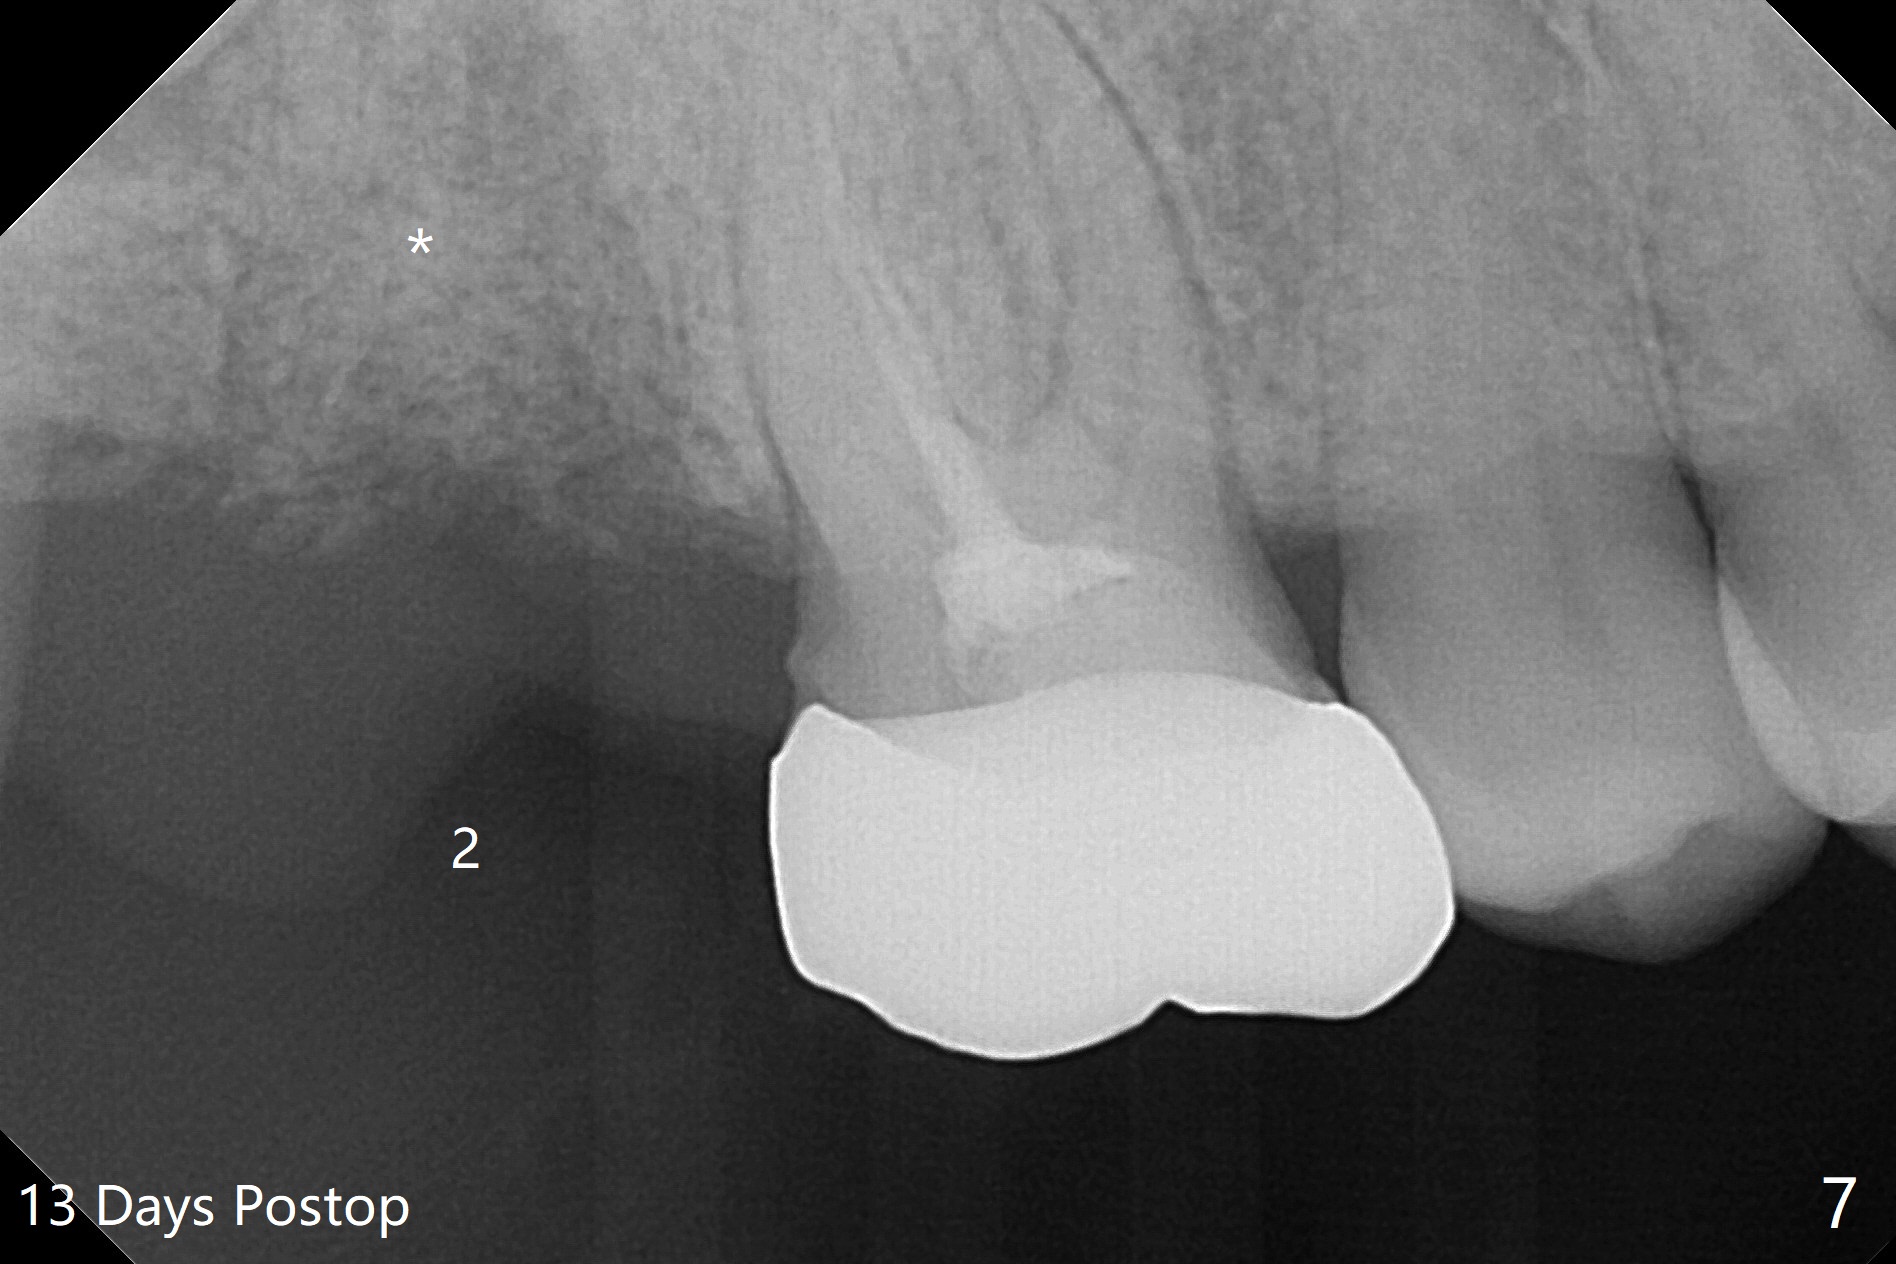

The socket of #2 heals 13 days postop; it appears that the bone graft remains in place (Fig.7,8 *). The patient is instructed to return in 3-4 months for impression and CT for guide. The socket heals 4 months postop (Fig.9,10). She plans to have implant next year, since she wants to add another insurance. The patient returns for implant without removal of the third molar 2 years 4 months post socket preservation (Fig.11). A 5x7.3 mm implant can be placed without invading the sac of the impacted third molar (Fig.12). In fact the lab has a better plan. A lump of bone forms in the previous socket 1 year 4 months postop (Fig.13 *). The ridge is wide and dense (Fig.14). A narrow implant placed oblique could be longer (Fig.15), as compared to a wide, short one (Fig.12).